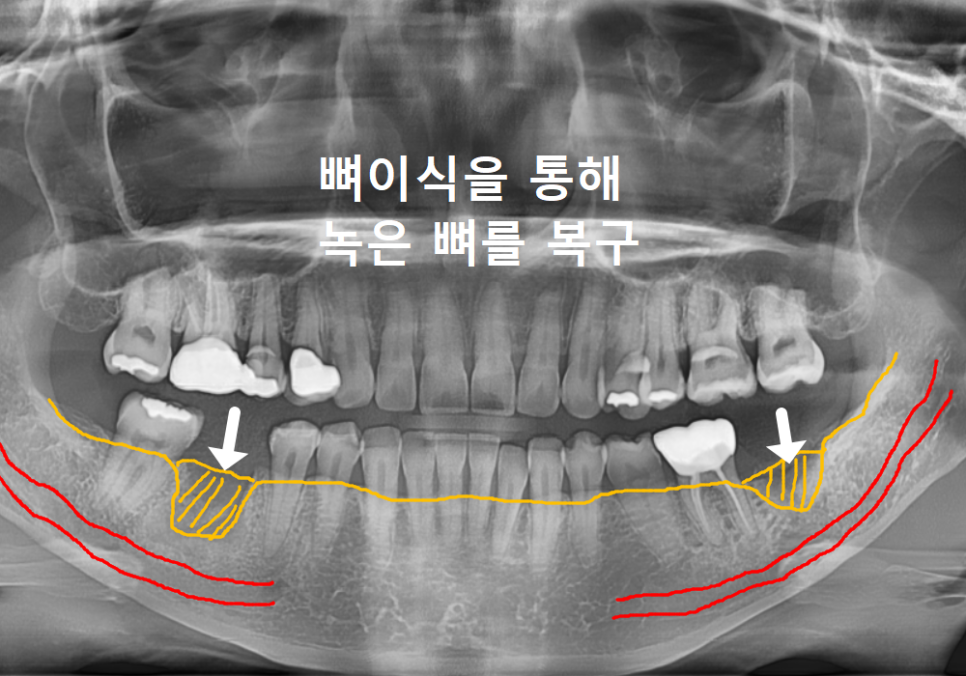

그래서 뼈이식이

필요한 겁니다.

이 환자분도 발치 후 부족한 공간을 채워줄

'뼈이식'을 먼저 진행했습니다.

녹아내린 자리에 뼈이식 재료를 채워 넣어

임플란트를 든든하게 지지해 줄

땅을 만든다고 생각하면 됩니다.

이때 뼈이식만큼이나 중요한 게 있는데요,

바로 '기다림'입니다.

이식한 뼈가 자가골과 엉겨 붙어

단단하게 굳을 시간이 필요하거든요.